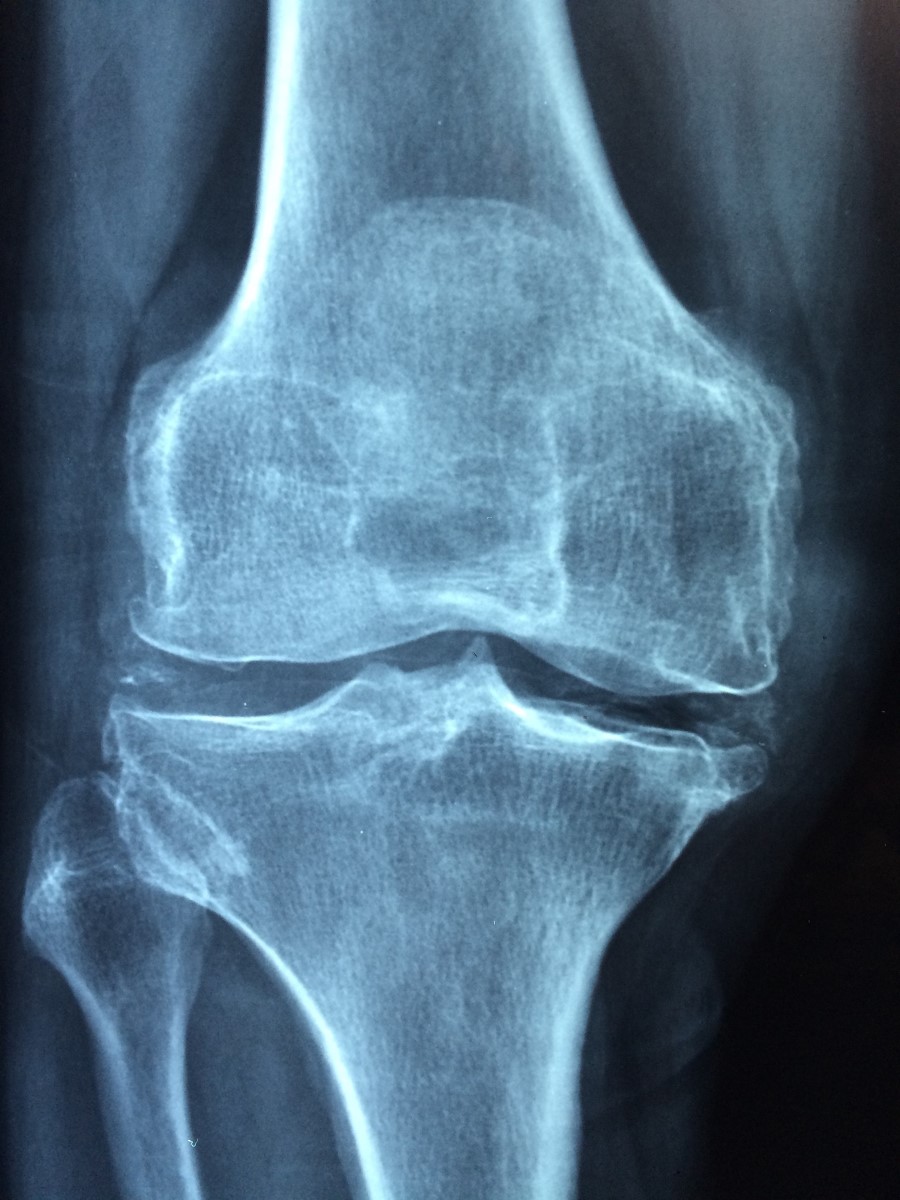

Co když mám už diagnostikovanou artrózu?

Strava a návyky mohou ulevit, ale léčbu nenahrazují. Konzultujte s lékařem/fyzioterapeutem. Zaměřte se na váhu, sílu středu těla a pravidelný pohyb bez bolesti.